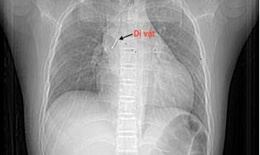

Cụ ông 90 tuổi nguy kịch sau bữa cơm tối

Camera bệnh viện - 06/10/2025 17:07SKĐS - Bệnh viện Bệnh Nhiệt đới Trung ương vừa cứu sống thành công cụ ông N.V.S (90 tuổi, ở Hà Nội) bị tắc nghẽn đường thở trong lúc ăn tối.